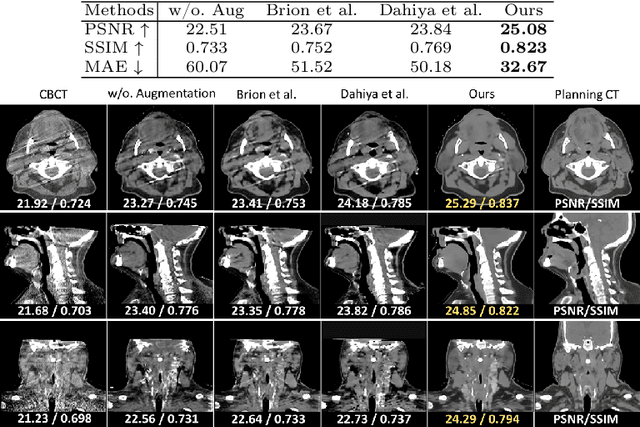

Abstract:Cone Beam Computed Tomography (CBCT) finds diverse applications in medicine. Ensuring high image quality in CBCT scans is essential for accurate diagnosis and treatment delivery. Yet, the susceptibility of CBCT images to noise and artifacts undermines both their usefulness and reliability. Existing methods typically address CBCT artifacts through image-to-image translation approaches. These methods, however, are limited by the artifact types present in the training data, which may not cover the complete spectrum of CBCT degradations stemming from variations in imaging protocols. Gathering additional data to encompass all possible scenarios can often pose a challenge. To address this, we present SinoSynth, a physics-based degradation model that simulates various CBCT-specific artifacts to generate a diverse set of synthetic CBCT images from high-quality CT images without requiring pre-aligned data. Through extensive experiments, we demonstrate that several different generative networks trained on our synthesized data achieve remarkable results on heterogeneous multi-institutional datasets, outperforming even the same networks trained on actual data. We further show that our degradation model conveniently provides an avenue to enforce anatomical constraints in conditional generative models, yielding high-quality and structure-preserving synthetic CT images.